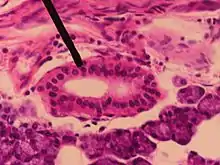

Section of submaxillary gland of kitten. Duct semidiagrammatic. X 200.

Section of submaxillary gland of kitten. Duct semidiagrammatic. X 200. Section of portion of mamma.